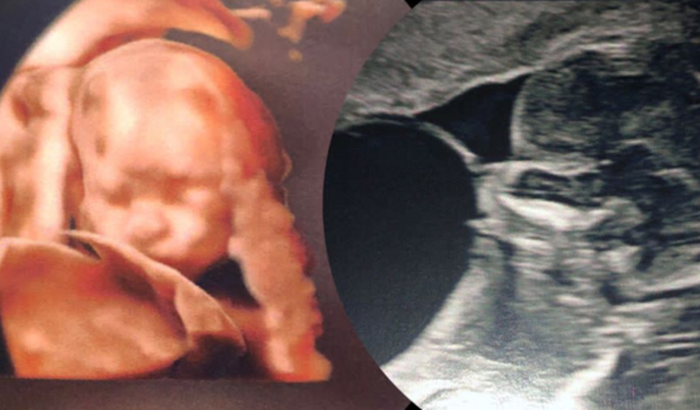

Tudo começou na primeira ecografia morfológica no dia 09/02, houve a suspeita de uma má formação muito rara que se chama Megabexiga. Meus pais ficaram muito assustados, mas isso era só o começo. Ganhamos um encaminhamento para acompanhamento em Porto Alegre, porém ainda não obtivemos retorno do agendamento da minha consulta, então, decidimos ir no Instituto Materno Fetal que fica no Hospital Santa Casa e pagar particular uma consulta de avaliação. No dia 20/02, dois dias antes do aniversário da minha mãe, tivemos a primeira consulta, foi constatado a má formação como Megabexiga- Válvula da Uretra Posterior/Anterior, essa má formação impede que o xixi produzido por mim saia da minha bexiga, o que acarreta perda da função renal, má formação dos pulmões, sobrecarregando o coração e por fim, falência múltipla dos órgãos. Tenho poucas chances de sobreviver e caso eu nasça teria muitos problemas, tanto respiratórios, quanto renais, além de precisar de diálise e transplantes. Eu necessitaria de uma cirurgia que custaria em média 50 mil reais em no máximo 3 semanas, infelizmente não foi possível e agora não é mais viável efetuar a mesma. Meus pais estão correndo na justiça para que eu possa ser acompanhado por especialistas sem custo, por enquanto continuamos consultando particular sempre que possível. Infelizmente, são duas consultas por mês no valor de 600 reais, fora exames laboratoriais, locomoção e alimentação.